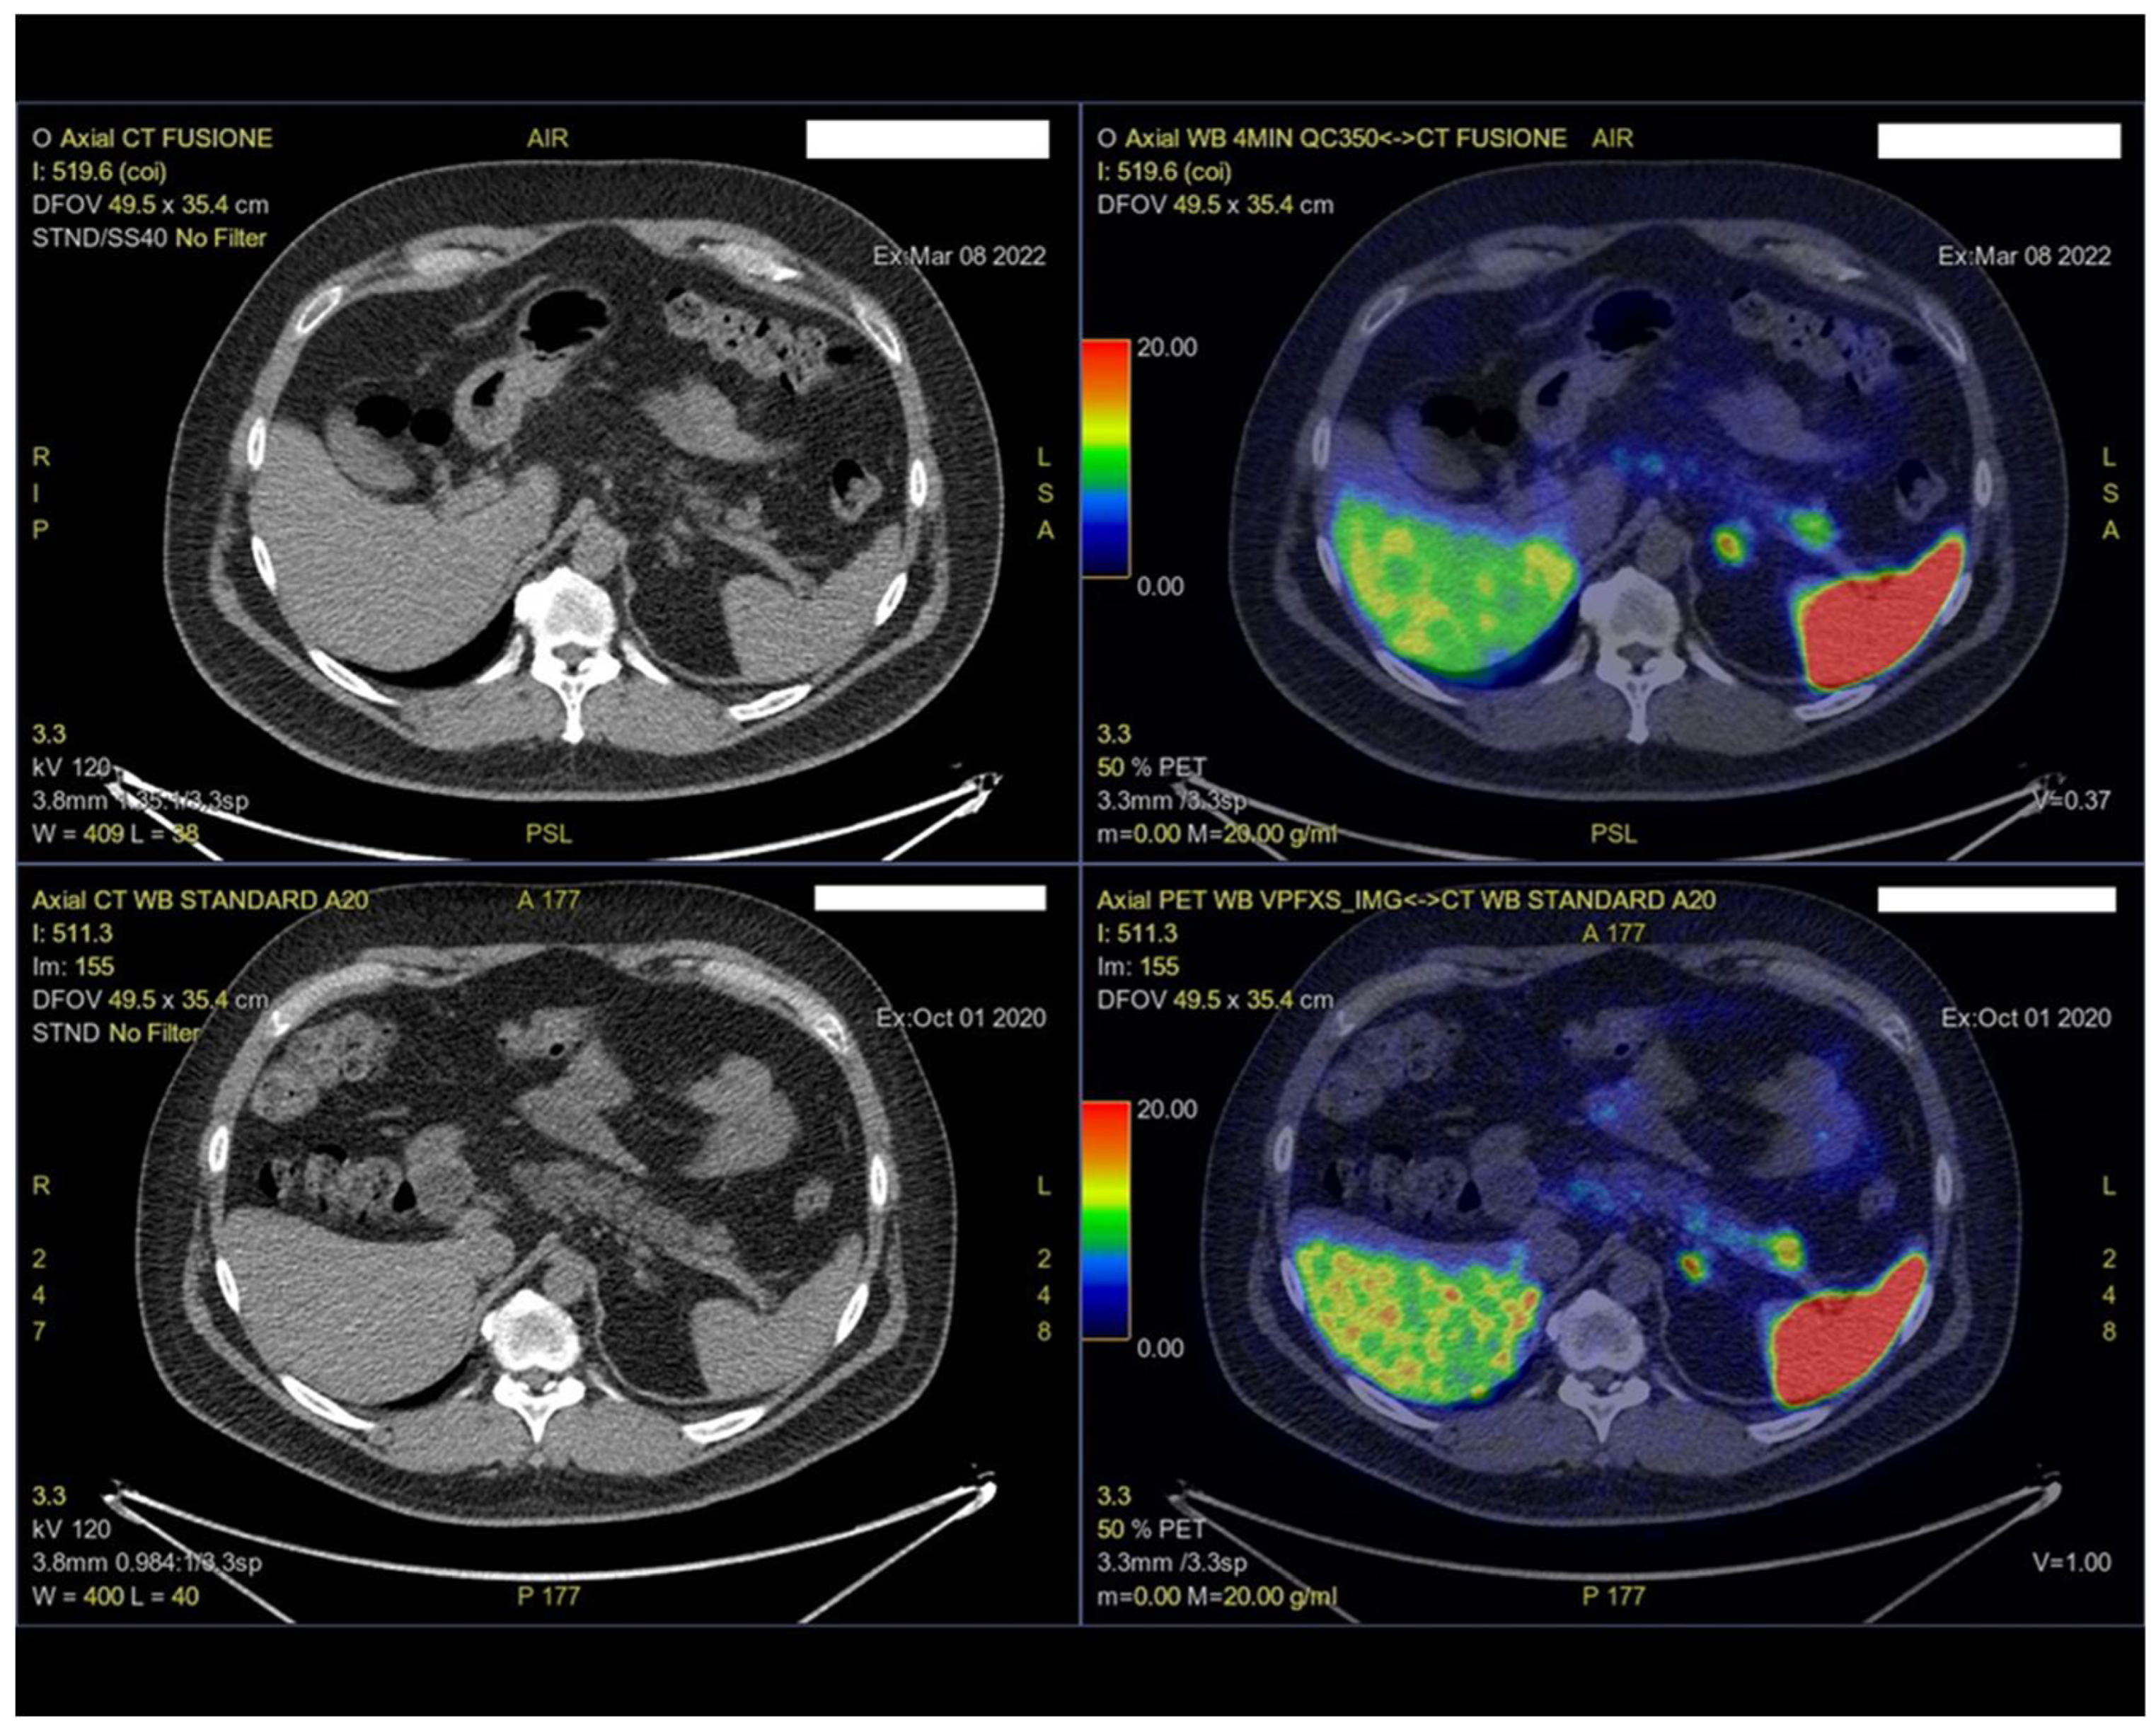

2. Case Presentation